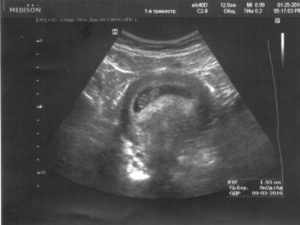

Для диагностики гипертонуса используется ультразвуковое исследование, при проведении которого может быть выявлен гипертонус задней стенки матки, а также передней. Однако, этот признак не всегда может говорить об угрозе прерывание беременности. Матка может прийти в тонус в ответ на прохождение ультразвуковой волны через ее стенку.

Также на ультразвуковом исследовании при выполнении цервикометрии (измерение длины шейки матки) диагностируется истмико-цервикальная недостаточность (укорочение шейки матки, открытие ее внутреннего зева).

Ультразвуковое исследование с допплерометрией даёт возможность детально подойти к диагностике. Определяется распространённость гипертонуса, наличие либо отсутствие ретрохориальной гематомы, оценивается кровоток в сосудах матки и плода.

Определить локальный гипертонус матки по задней или передней стенке можно с помощью ультразвукового исследования. При этом на УЗИ видно изменение стенки матки в месте её тонуса, она прогибается вовнутрь.